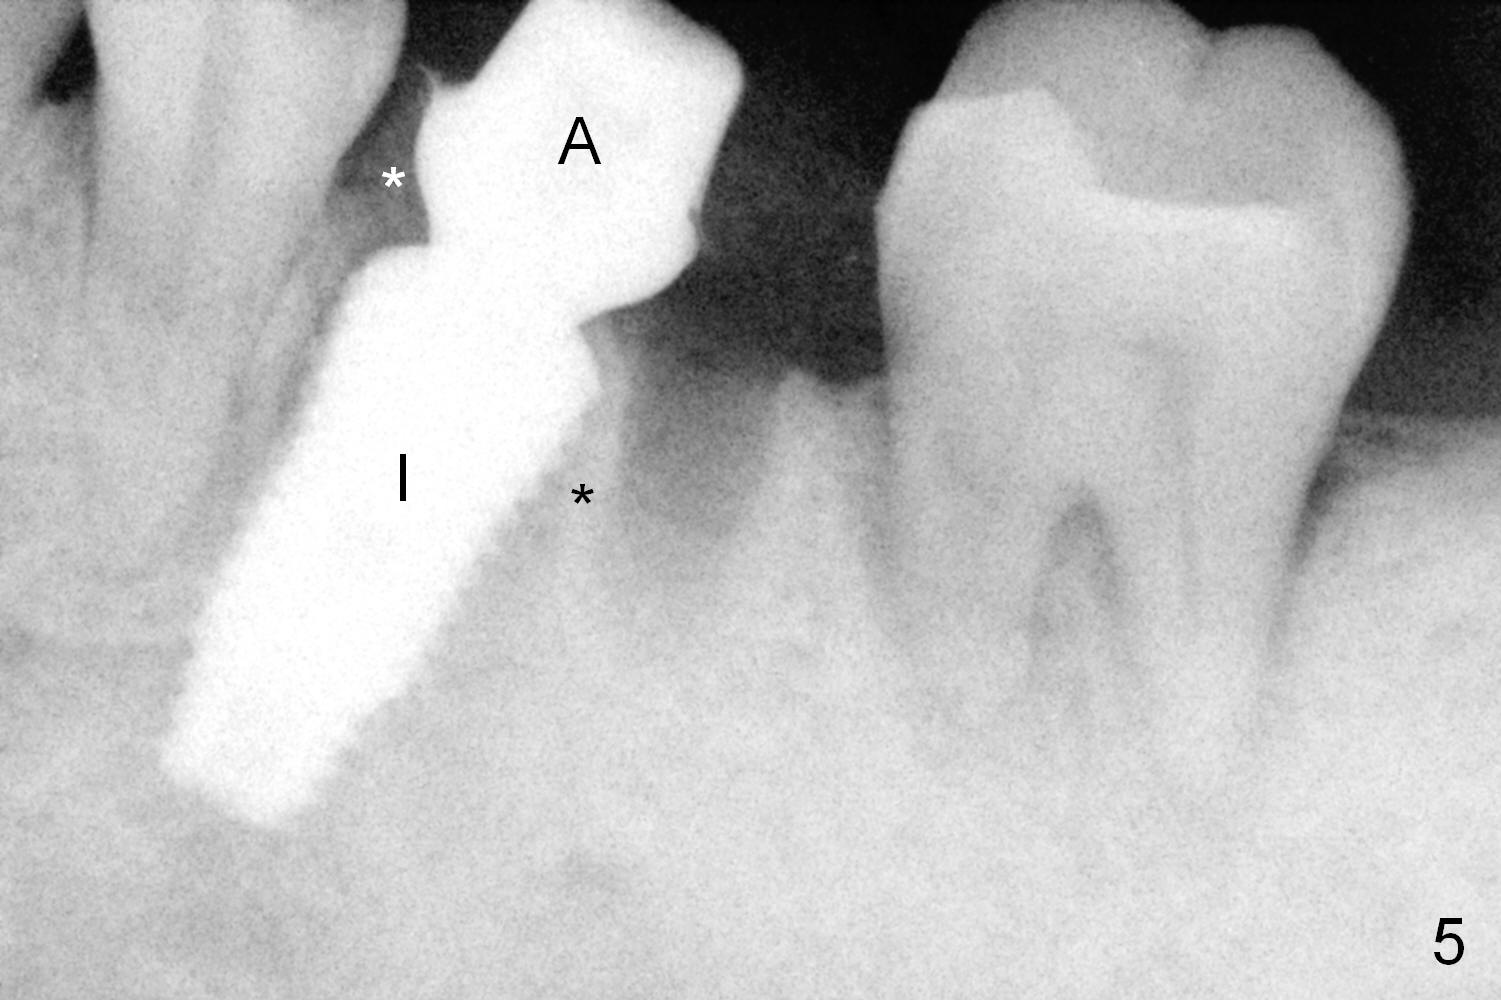

A fistula is found to be associated with the furca when the patient returns for extraction (Fig.1 <). Although the mesial socket is deeper than the distal one, no granulation tissue is curetted from the mesial. Osteotomy is set in the middle of the septum by making a slot first. When the osteotomy is enlarged by 4 mm reamer (Fig.2 R), the latter has been deviated mesial to the septum (*). By manipulating, the coronal end of 6x12 mm implant and 6.5x4(3) mm abutment (Fig.3 A) are placed somewhat in the middle of the socket. An immediate provisional is fabricated to cover the socket and bone graft (Fig.4 P). The exposed bone graft (Fig.4 *) is then covered by perio dressing. Off axial placement of the implant (Fig.5 I) and abutment (A) is striking in the immediately postop PA (Fig.5).

How to place the immediate implant in the middle of the septum? In addition to the slot in the middle, the smallest pilot drill should be used for limited depth and an early intraop PA should be taken (Fig.6). If the deviation is noted (Fig.6 red long arrow) in the septum (S), it should be corrected before using the next drill (Fig.7).